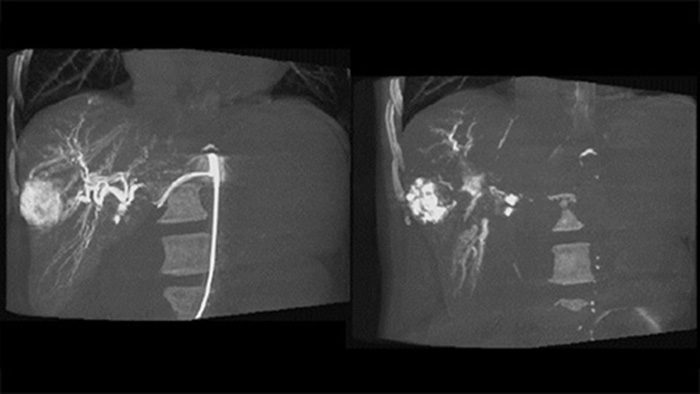

Une acquisition 3D post-embolisation permet de visualiser le dépôt ciblé du matériau embolique, tel que le Liopidol ou les microsphères radio-opaques, dans la tumeur.5

La fonction double affichage permet la visualisation simultanée de l’image 3D de la phase artérielle avant embolisation et de l’image après embolisation pour évaluer la fin du traitement.